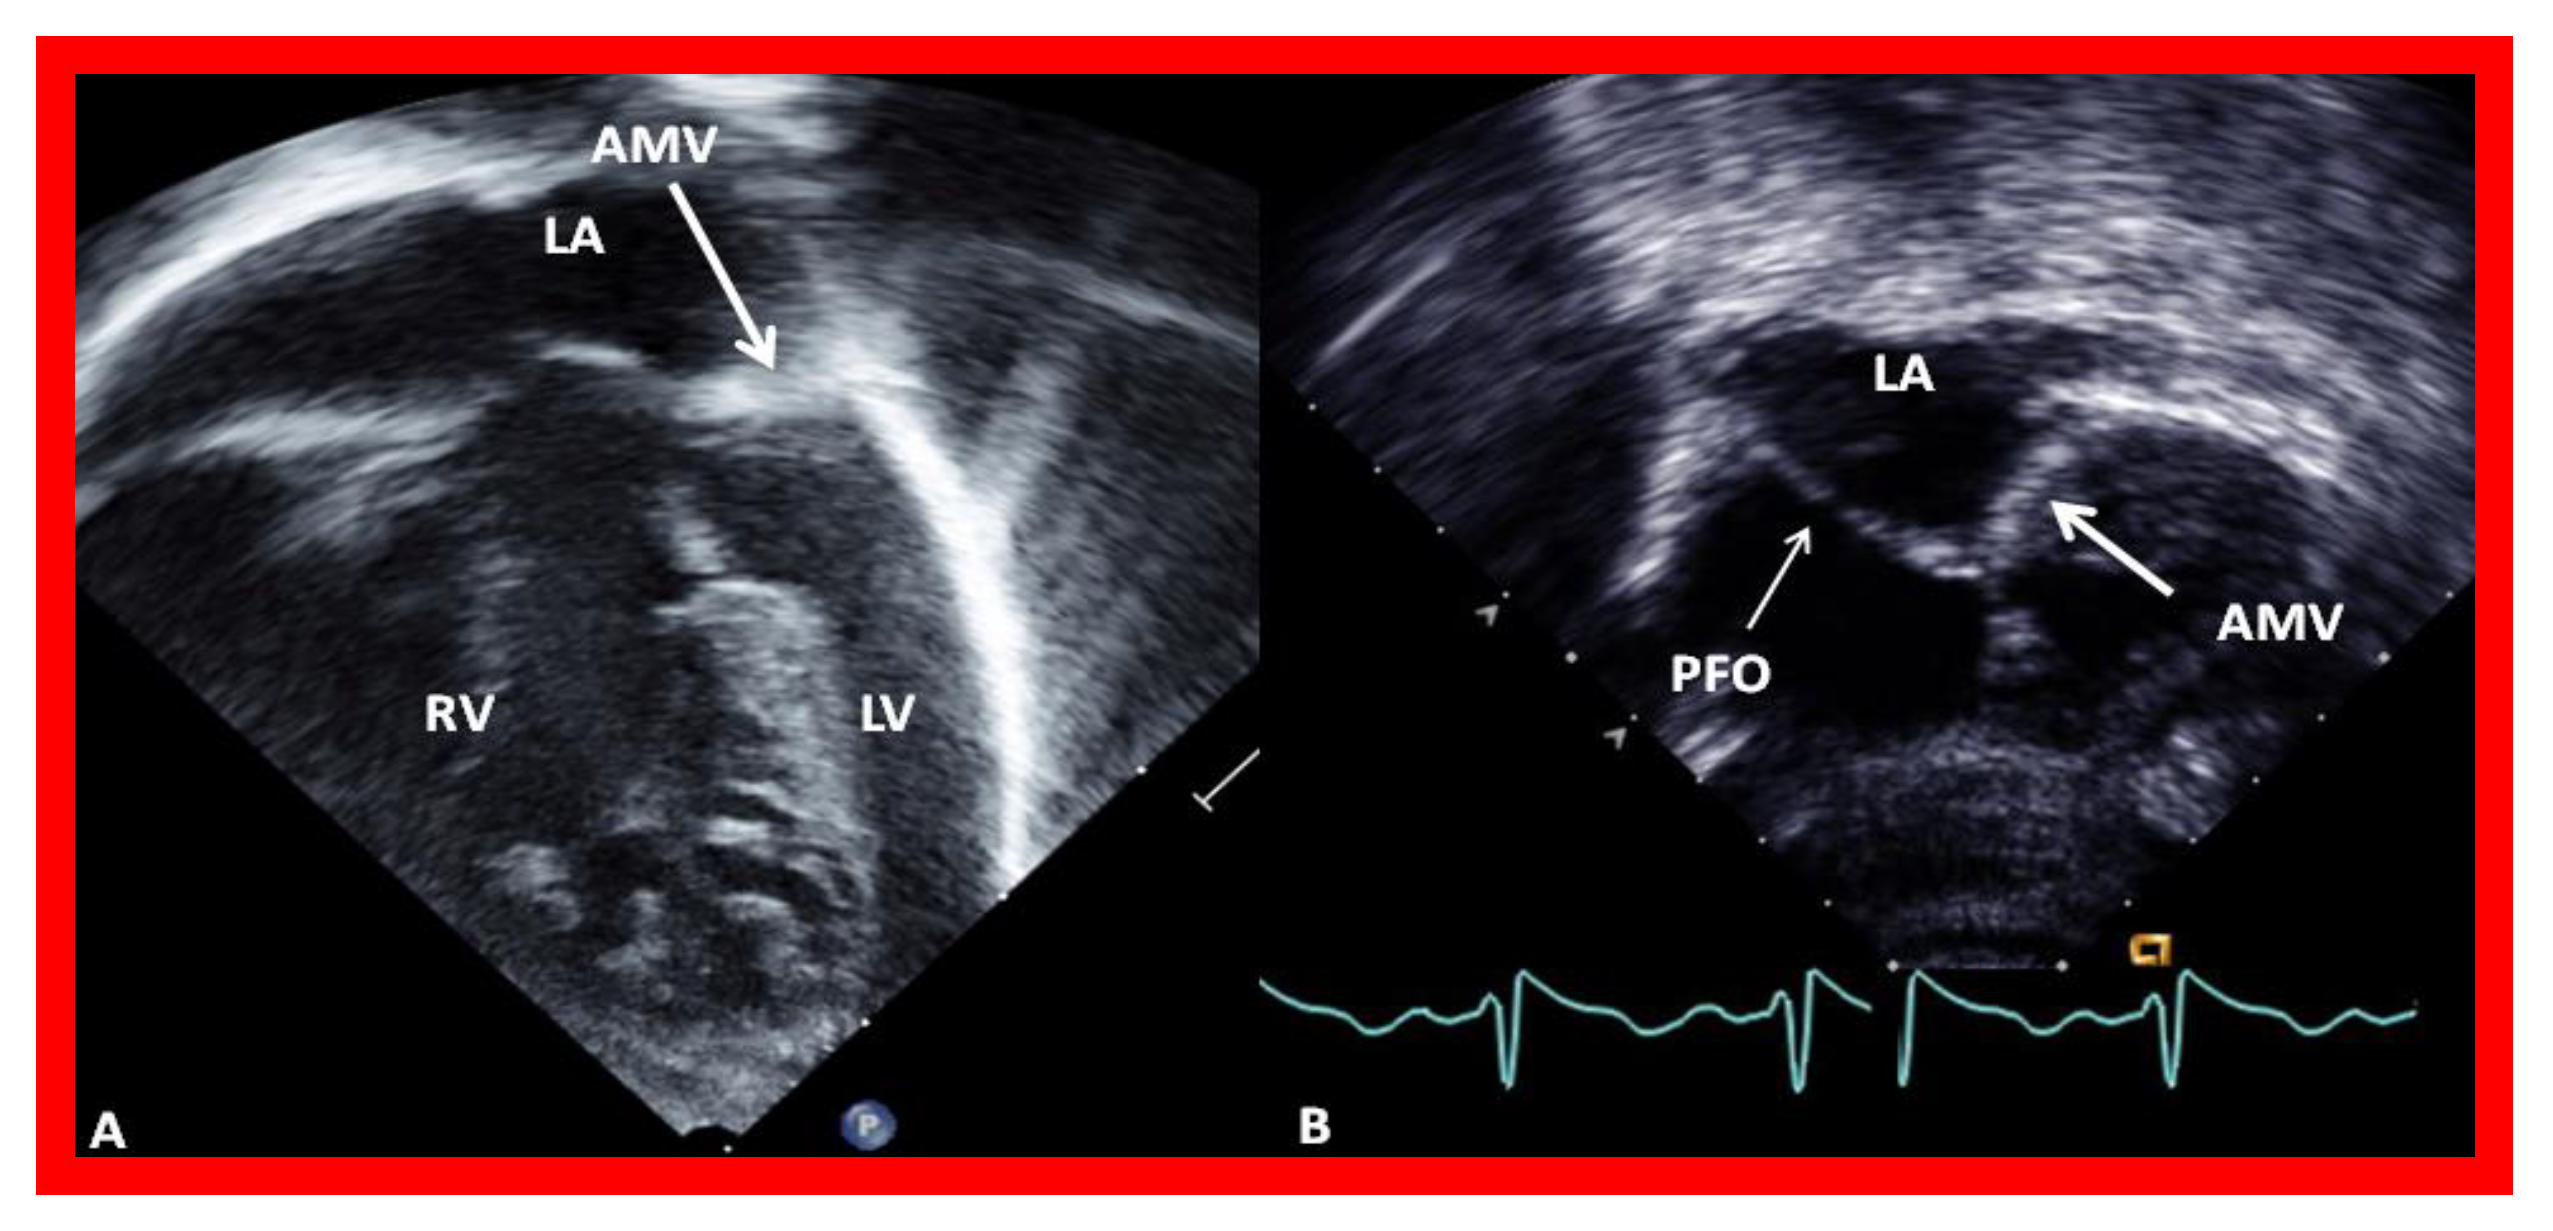

Figure 6.

Echocardiograms in modified four-chamber views of two infants with mitral atresia, demonstrating atretic mitral valves (AMV), indicated by thick arrows. A small left atrium (LA) and left ventricle (LV) and a large right ventricle (RV) are also seen. The thin arrow in (B) shows a restrictive patent foramen ovale (PFO). All four chambers were shown in (A) while (B) focuses on the atria. Reproduced from Reference [15].